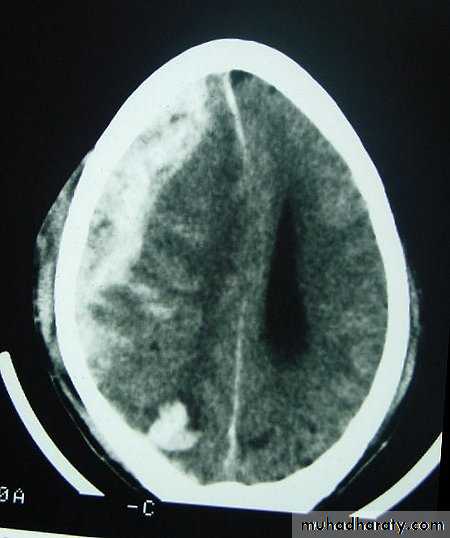

Chronic Subdural Haematoma

Most common in infants and in adults over 60 years of age secondary to SLIGHT blow to the head which may pass unnoticed.

Source of bleeding (haematoma): usually from bridging veins as they pass to the venous sinuses.

The patients present with progressive neurological deficits more than 3 weeks after the trauma.

The initial head injury is often completely forgotten.

CT scan: the acute clotted blood is initially appears white (hyperdence), but as it liquefies, it slowly becomes black (hypodense).

They should be drained if they continue to enlarge.

They are evacuated by drilling burrholes over the collection and washing it out with warmed saline.